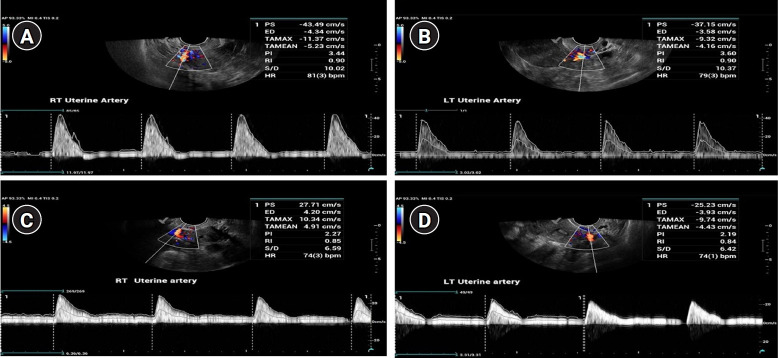

Methods: Between February and November 2023, our reproductive facility conducted a single-center randomized clinical trial, enrolling 100 patients with previous implantation failure and at least one uterine PI measurement exceeding 3. Participants were randomly assigned to receive either amlodipine (5 mg) or placebo (n=50 per group). Hormone replacement therapy was the predominant method for endometrial preparation. Transvaginal ultrasonography was used to measure uterine artery resistance and pulsatility on day 1 or 2 of menstruation. Women in the amlodipine group received 5 mg nightly. Following repeat transvaginal ultrasound to assess PI and RI, ET was performed. If a positive pregnancy test was obtained, treatment continued for a total of 7 weeks.

Results: Amlodipine reduced blood flow indices in the uterine artery. Among placebo recipients, 18% tested positive for beta-human chorionic gonadotropin, compared to 26% of medication recipients. However, this difference was statistically insignificant (p=0.472). Gestational sacs were observed in 12% of the placebo group and 22% of the medication group, but this difference was also insignificant (p=0.28).